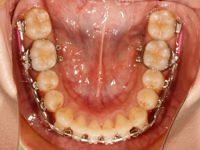

次は、調整後のお口の中の様子です![]()

見た目にはわかりませんが、今回も細かい所を調整しました![]()

今回も上顎の奥から2番目の歯を後ろに動かしています![]()

奥歯が動くのは非常にゆっくりなので変化はわかりにくいのですが、少しずつ変化しています![]()

下顎の方は、前回から引き続き奥から引っ張っています![]()